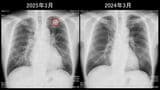

がん検診一筋の60代医師が「ステージ4」の進行がんに。《毎年検診を受けていたのに…》それでも「やっぱり検診は必要」揺るがぬ考えの写真一覧

がん検診の第一人者でありながら、自身も突然「進行がん」と診断された医師・松田一夫さん。日本のがん死亡率が高止まりする背景には、検診制度の“ゆるさ”と受診率の壁が存在します。30年にわたりがん検診を研究・実践してきた松田医師が語る、見過ごされがちな現場の課題と、今私たちに問われる“検診”の意味とは?(このリード文はAIが作成しました)